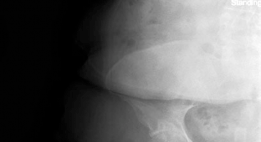

Clinical & Radiographic Imaging